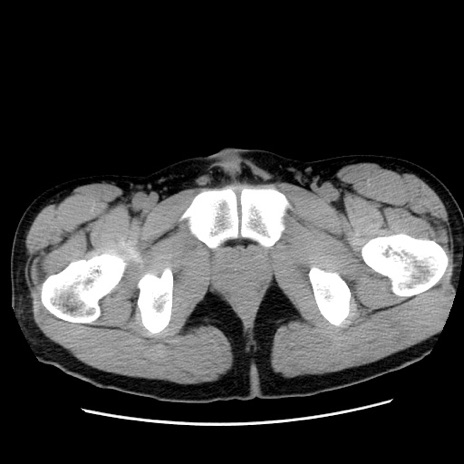

症例36(横断像)

【症例】20歳代 男性

【主訴】心窩部痛

【現病歴】今朝より上腹部痛あり。一旦軽快していたが再度出現したため救急要請。昨日夕に白身の魚を含む刺身を食べた。

【身体所見】BP 136/89mmHg、HR 74/min、BT 37.0℃、腹部:膨満、軟、心窩部に圧痛あり。反跳痛なし、筋性防御なし、腸雑音やや亢進あり。

【データ】WBC 17700、CRP 0.48